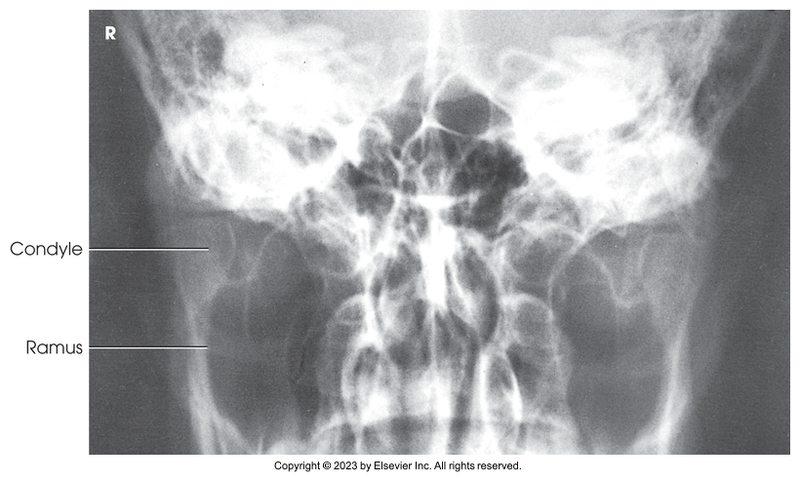

AP axial of the TMJs

AP axial of temporomandibular joint (mouth closed)

AP axial of temporomandibular joint (mouth opened)